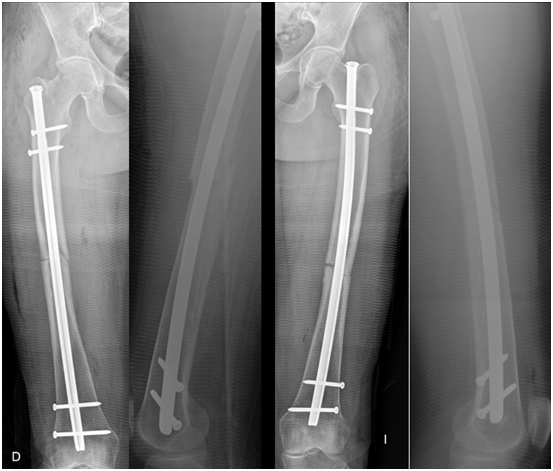

The load without a walker was achieved after 3.5 months, but the patient used a cane because she reported pain in the left thigh. At 6 months the patient wandered without help, with sporadic discomfort, the radiographs showed signs of consolidation and the patient gradually returned to their usual activities, but as activity increased, they began again with intermittent pain in the left thigh, new radiographs were taken and the patient was observed delay of the consolidation reason why the dynamization of both femurs is decided at eight months post surgical.

The consolidation of the right femur was completed at 11 months, no longer had pain or discomfort in the femur but continued with pain in the left thigh, new radiographs were made showing hypertrophic pseudoarthrosis so it was decided to perform a new surgery and place a plate blocked with minimally invasive technique on the nail, with this procedure immediate pain relief is achieved, full load was allowed after 2 weeks and consolidation was achieved 3 months later (Figure 4). Currently, the patient is 2.5 years old and does not present any pain or limitation in hip and knee mobility (Figure 5).

Figure 4 A) 6 months PO. B) 11 months PO: consolidation femur der. Plate MIO femur left.